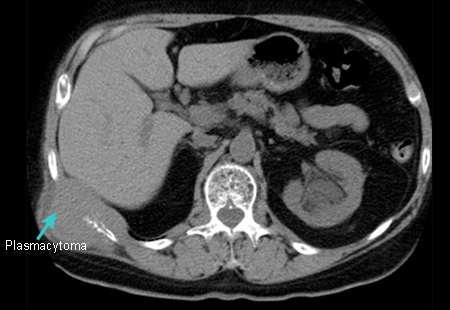

Evaluation of monoclonal gammopathies

Plasmacytoma

From the personal collection of Dr Kumar